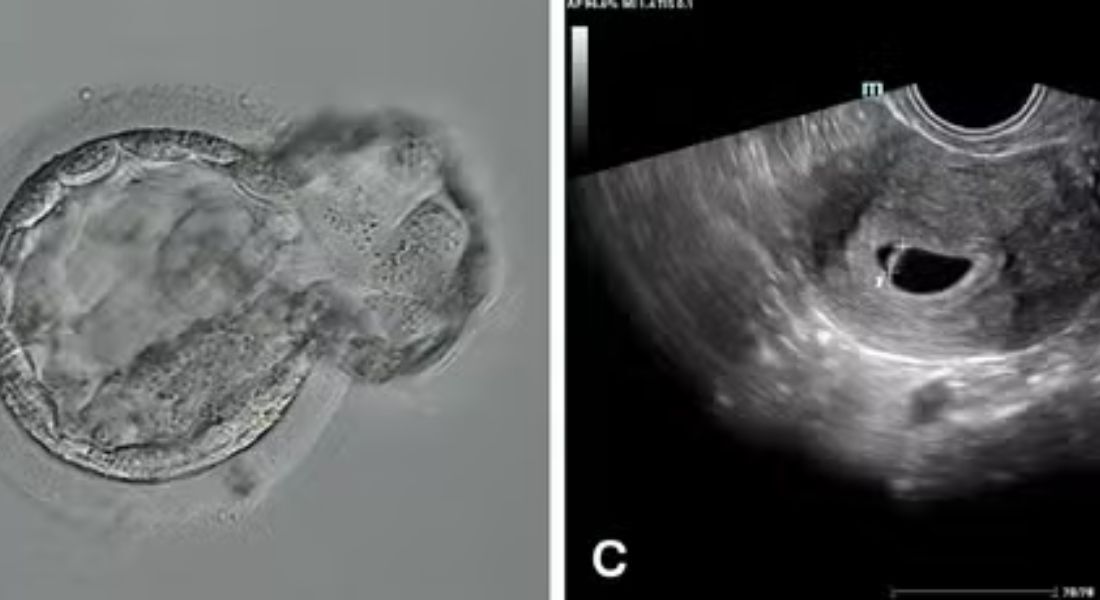

Quatro dos cinco óvulos injetados no sistema automatizado obtiveram fertilização normal, e todos os três no grupo de controle manual. Um embrião de alta qualidade, que progrediu para o estágio de blastocisto em cultura, havia sido fertilizado com o sistema automatizado sob controle remoto em Nova York, a 3.700 km de distância.

Após a transferência desse blastocisto vitrificado e depois descongelado em um ciclo subsequente, foi estabelecida uma gestação que continuou normalmente até o nascimento de um bebê do saudável do sexo masculino.